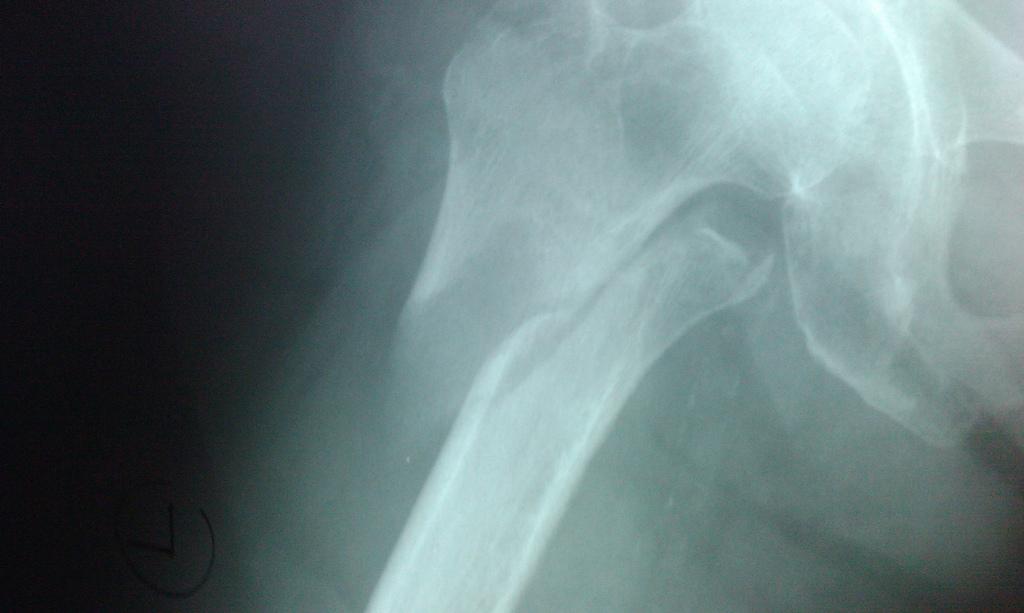

40. Detachable Hip

My dad is an orthopedic surgeon who does a lot of hips and knees. He cries with laughter every time he tells the story of a woman who didn’t understand how hip surgery works and thought they were going to take her leg off, fix the hip, and then reattach her leg.